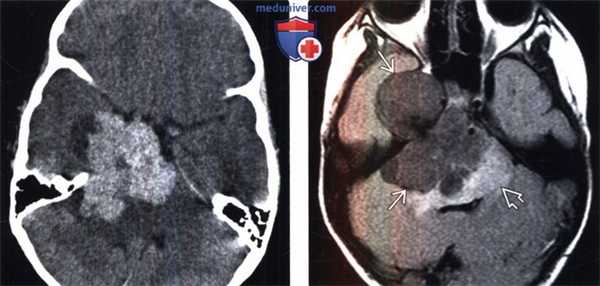

(Слева) Бесконтрастная КТ, аксиальный срез: определяется дольчатое гиперденсное объемное образование, расположенное по ходу намета мозжечка справа.

(Справа) МРТ, FLAIR, аксиальный срез: у этого же пациента визуализируется гипоинтенсивное многодольчатое объемное образование с перифокальным отеком и масс-эффектом на IV желудочек.